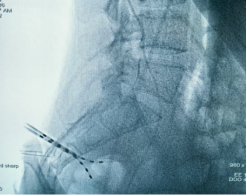

2026年1月30日,完善術(shù)前準(zhǔn)備后,手術(shù)于全麻并全程電生理監(jiān)測下進(jìn)行,歷經(jīng)5小時苦戰(zhàn),順利于腰膨大處置入外科電極一枚,雙側(cè)骶3孔各植入一根穿刺電極,連接2枚刺激器后埋置于皮下。手術(shù)實(shí)施順利,術(shù)中X線檢查植入位置良好。目前患者生命體征平穩(wěn),已開機(jī)測試,后期動態(tài)調(diào)整刺激參數(shù),并結(jié)合非侵入式腦機(jī)接口鍛煉。

雙側(cè)骶3孔順利植入穿刺電極